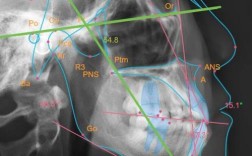

病例分析是直播的核心板块之一,曾教授会选取典型病例(如严重拥挤、开颌、深覆颌等)进行全流程复盘,包括患者初诊照片(口内口外)、X线头影测量数据分析、阶段性矫治效果对比及最终保持方案设计,针对治疗中的失败案例或并发症(如牙根吸收、复发问题),也会坦诚剖析原因,如何规避风险”“如何与患者有效沟通预期”等临床经验,强调正畸治疗不仅是“排齐牙齿”,更是“功能与美学的平衡”。

| 技术进阶 | 隐形附件设计、骨性畸形矫正技术、数字化方案设计、并发症处理 | 病例拆解、操作视频、数据图表 | 成人骨性龅牙的掩饰性正畸方案设计;扭转牙纠正技巧 |

| 病例实战 | 典型病例全流程复盘(初诊-治疗-保持)、失败案例反思、医患沟通要点 | 病例影像展示、阶段效果对比 | 严重拥挤病例的拔牙与非拔牙方案选择;开颌病例的病因分析 |